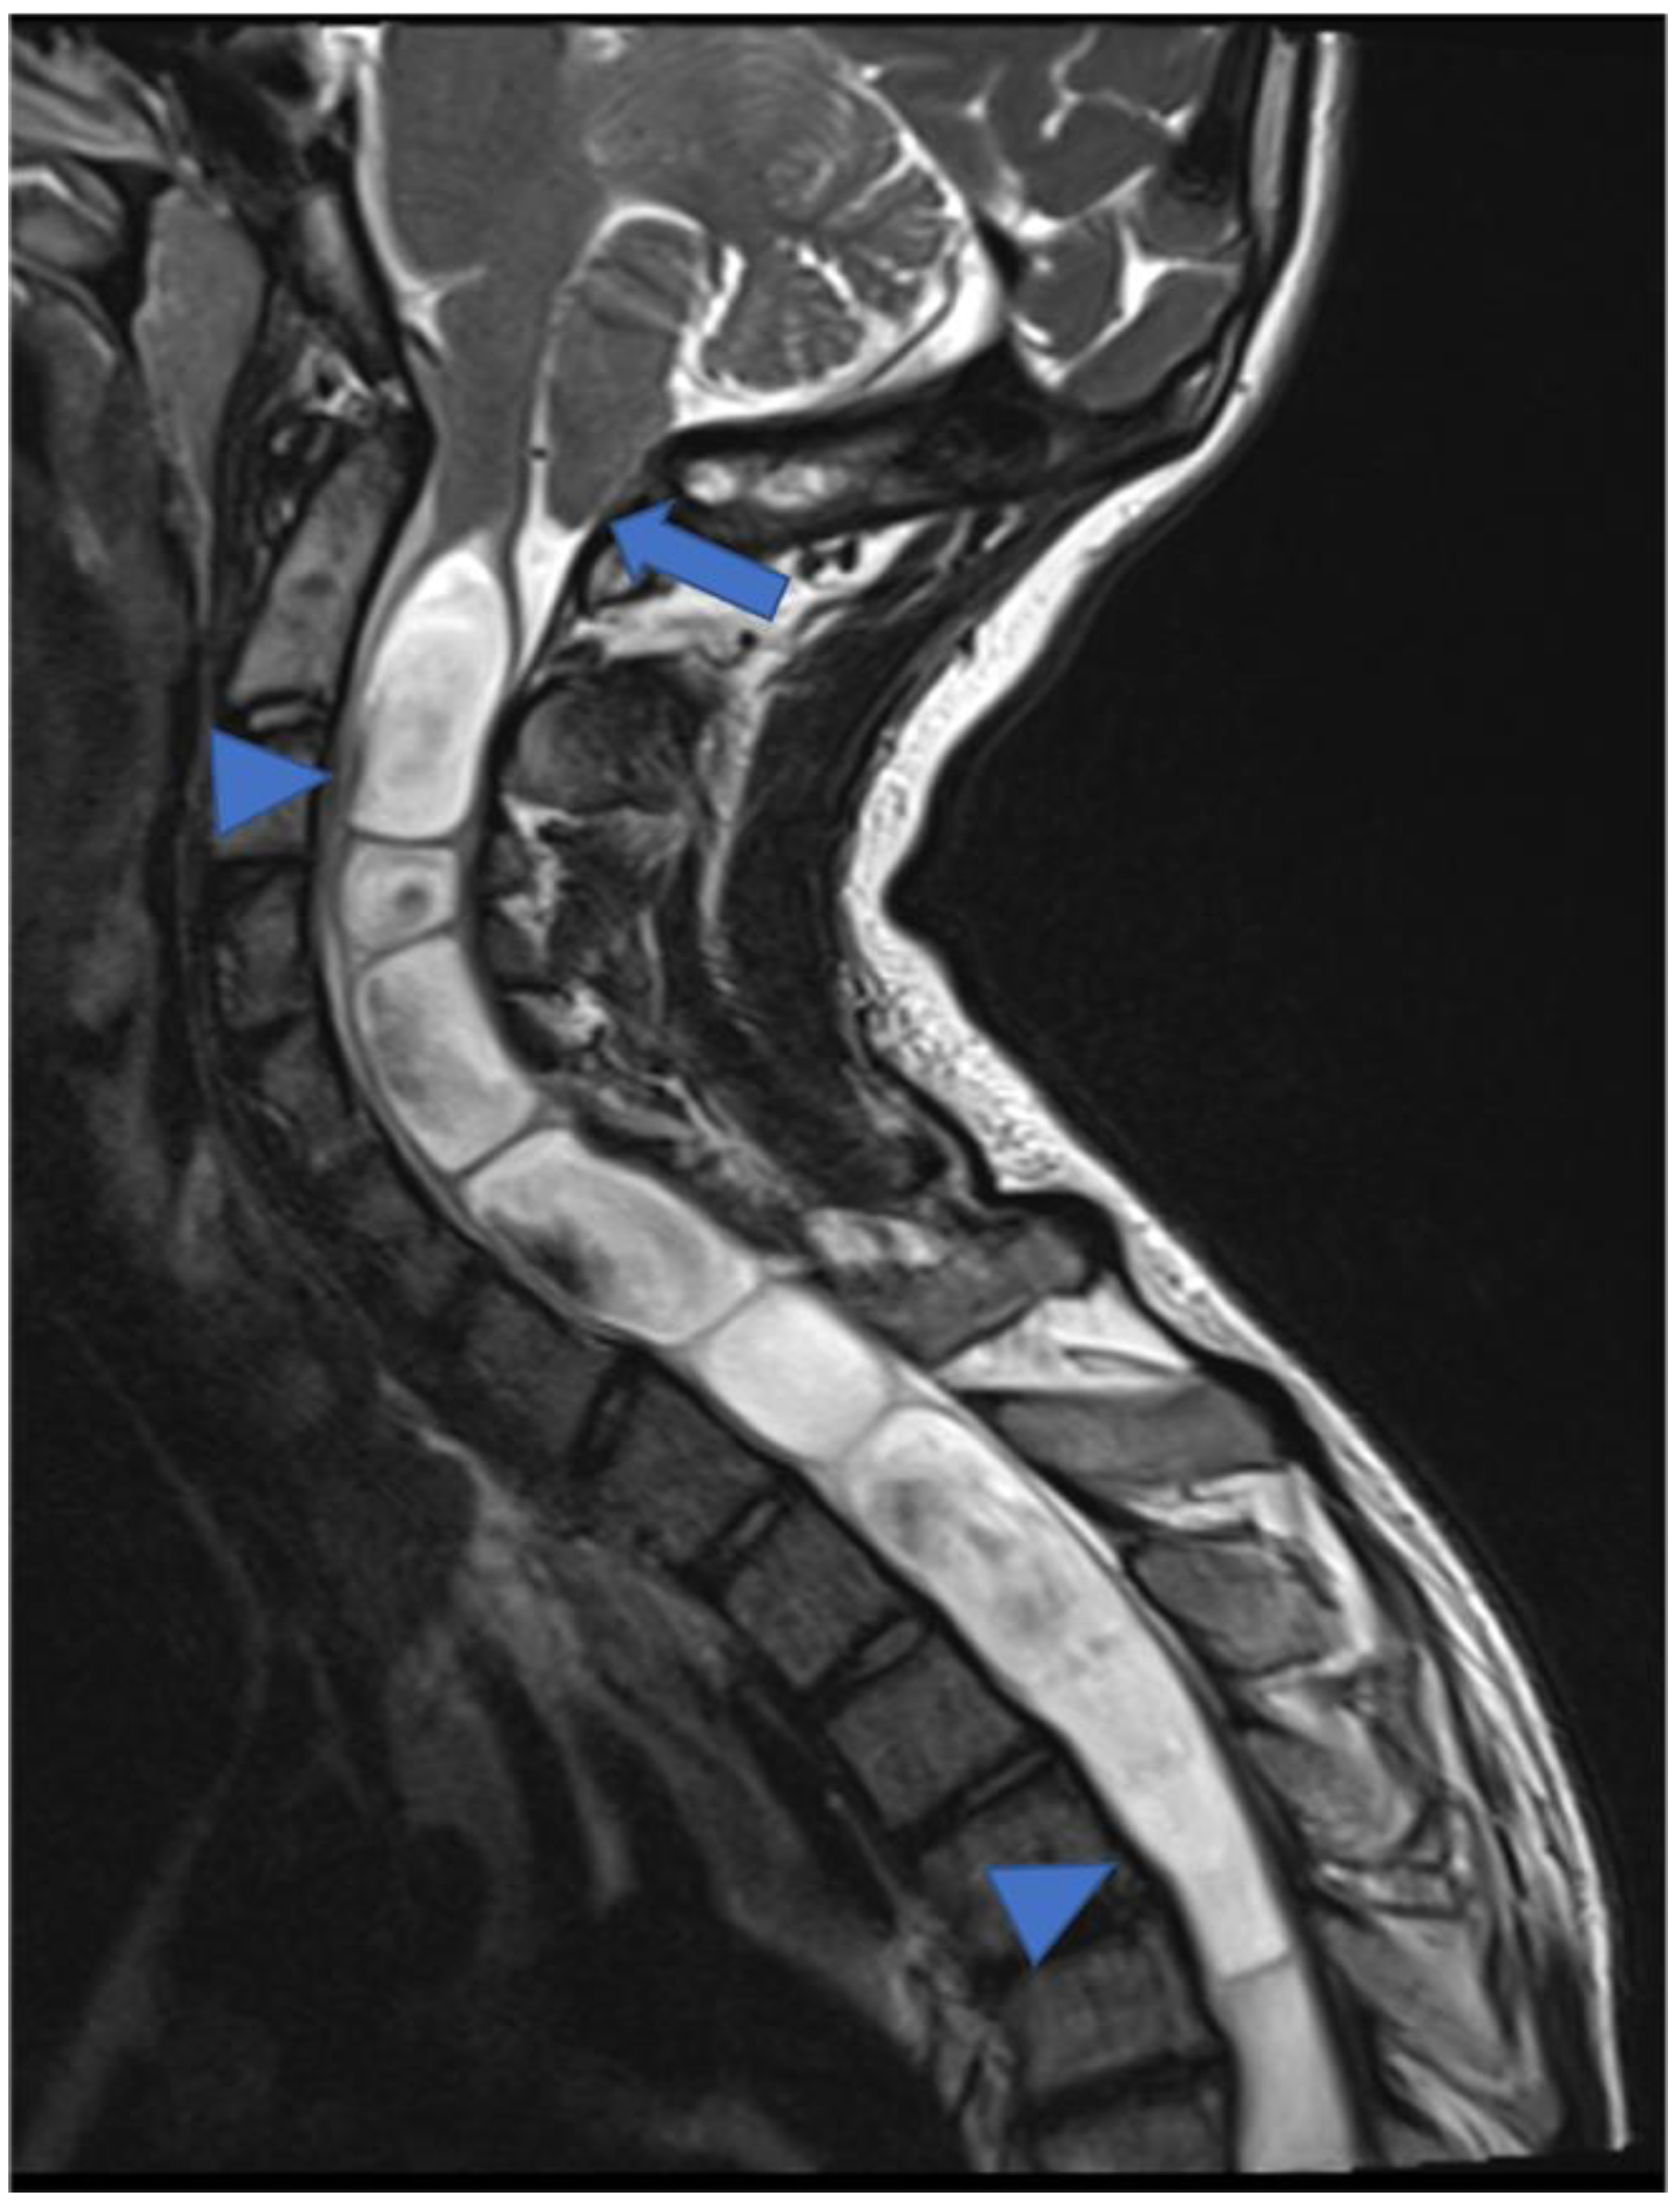

2. Gliomas and Mixed Neuronal–Glial Tumors

2.1. Gliomas